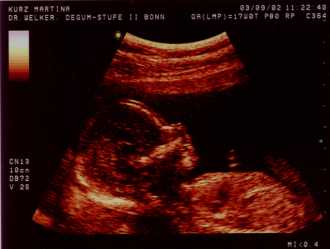

Wer Clemens nicht erkennt: Maus übers Bild ;-)